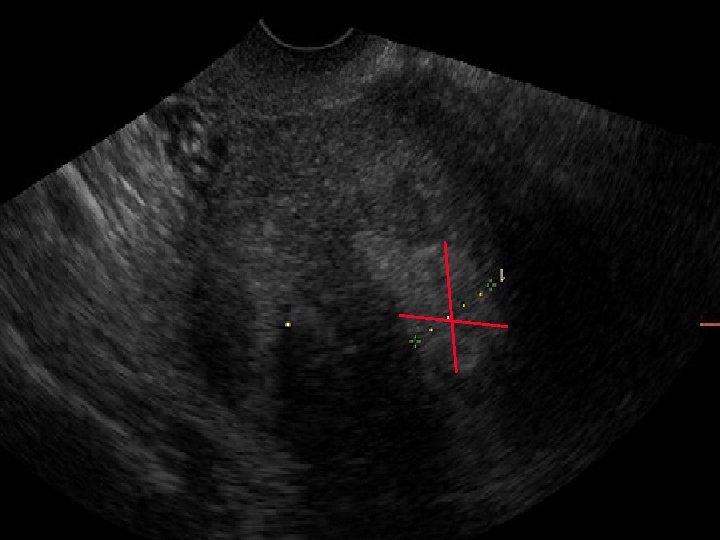

CARCINOMA ENDOMETRIALE 2. IMMAGINE SCANSIONE TRASVERSALE: SPESSORE ENDOMETRIALE 12 mm. BORDI IRREGOLARI CAUSATI DALL’INFILTRAZIONE MIOMETRIALE

5. VASCOLARIZZAZIONE POWER DOPPLER RI VASCOLARIZZAZIONE RI < 0, 5